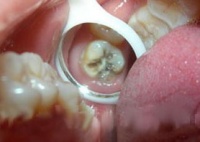

龋齿最容易发生在磨牙双尖牙的咬面小窝、裂沟中,以及相邻牙齿的接触面。前者称为窝沟龋,后者称为邻面龋。儿童发生在牙颈部的龋齿极少,只在严重营养不良或某些全身性疾病使体质极度虚弱时才可见到。根据龋齿破坏的程度,临床可分为浅龋、中龋和深龋。

• 浅龋 龋蚀破坏只在釉质内,初期表现为釉质出现褐色或黑褐色斑点或斑块,表面粗糙。继而形成表面破坏。邻面龋开始发生在接触面下方,窝沟龋则多开始在沟内,早期都不容易看到。只有发生在窝沟口时才可以看到,但儿童牙齿窝沟口处又容易有食物的色素沉着,医师检查不仔细也会误诊或漏诊。浅龋没有自觉症状

• 中龋:龋蚀已达到牙本质,形成牙本质浅层龋洞。病儿对冷水、冷气或甜、酸食物会感到牙齿酸痛,但刺激去掉以后,症状立即消失。这是在为牙本质对刺激感觉过敏的缘故。中龋及时得到治疗效果良好。

• 深龋:龋蚀已达到牙本质深层,接近牙髓,或已影响牙髓。患儿对冷、热、酸、甜都有痛感,特别对热敏感,一败涂地去掉以后,疼痛仍持续一定时间才逐渐消失。这时多数需要作牙髓治疗以保存牙齿。

治疗龋齿的主要方法是补牙充填。即将龋坏组织去除净,作成一定的洞形,清洗、消毒以后,用充填材料(filling materrial)填充,并恢复牙齿缺损的外形,龄坏即可不继续发展。浅龋充填效果最好。中龋和深龋的治疗,在去净龋坏组织以后,有时洞底已接近牙髓,就需要在洞底加一层护髓剂再填初。有时深龋在去净龋坏组织以后牙髓就暴露了,就需要先采取牙髓治疗,然后才能填充。充填材料主要用银汞合金(amalgam)或复合充填树脂(composite resin)。乳牙因要换牙,可以用玻璃离子水门汀(glass sonomer cement)填补(暂时性充填材料)。 如果蛀牙的部分较大,可能就要使用牙套修补,情况最严重时,要把蛀牙拔掉,继而换上假牙